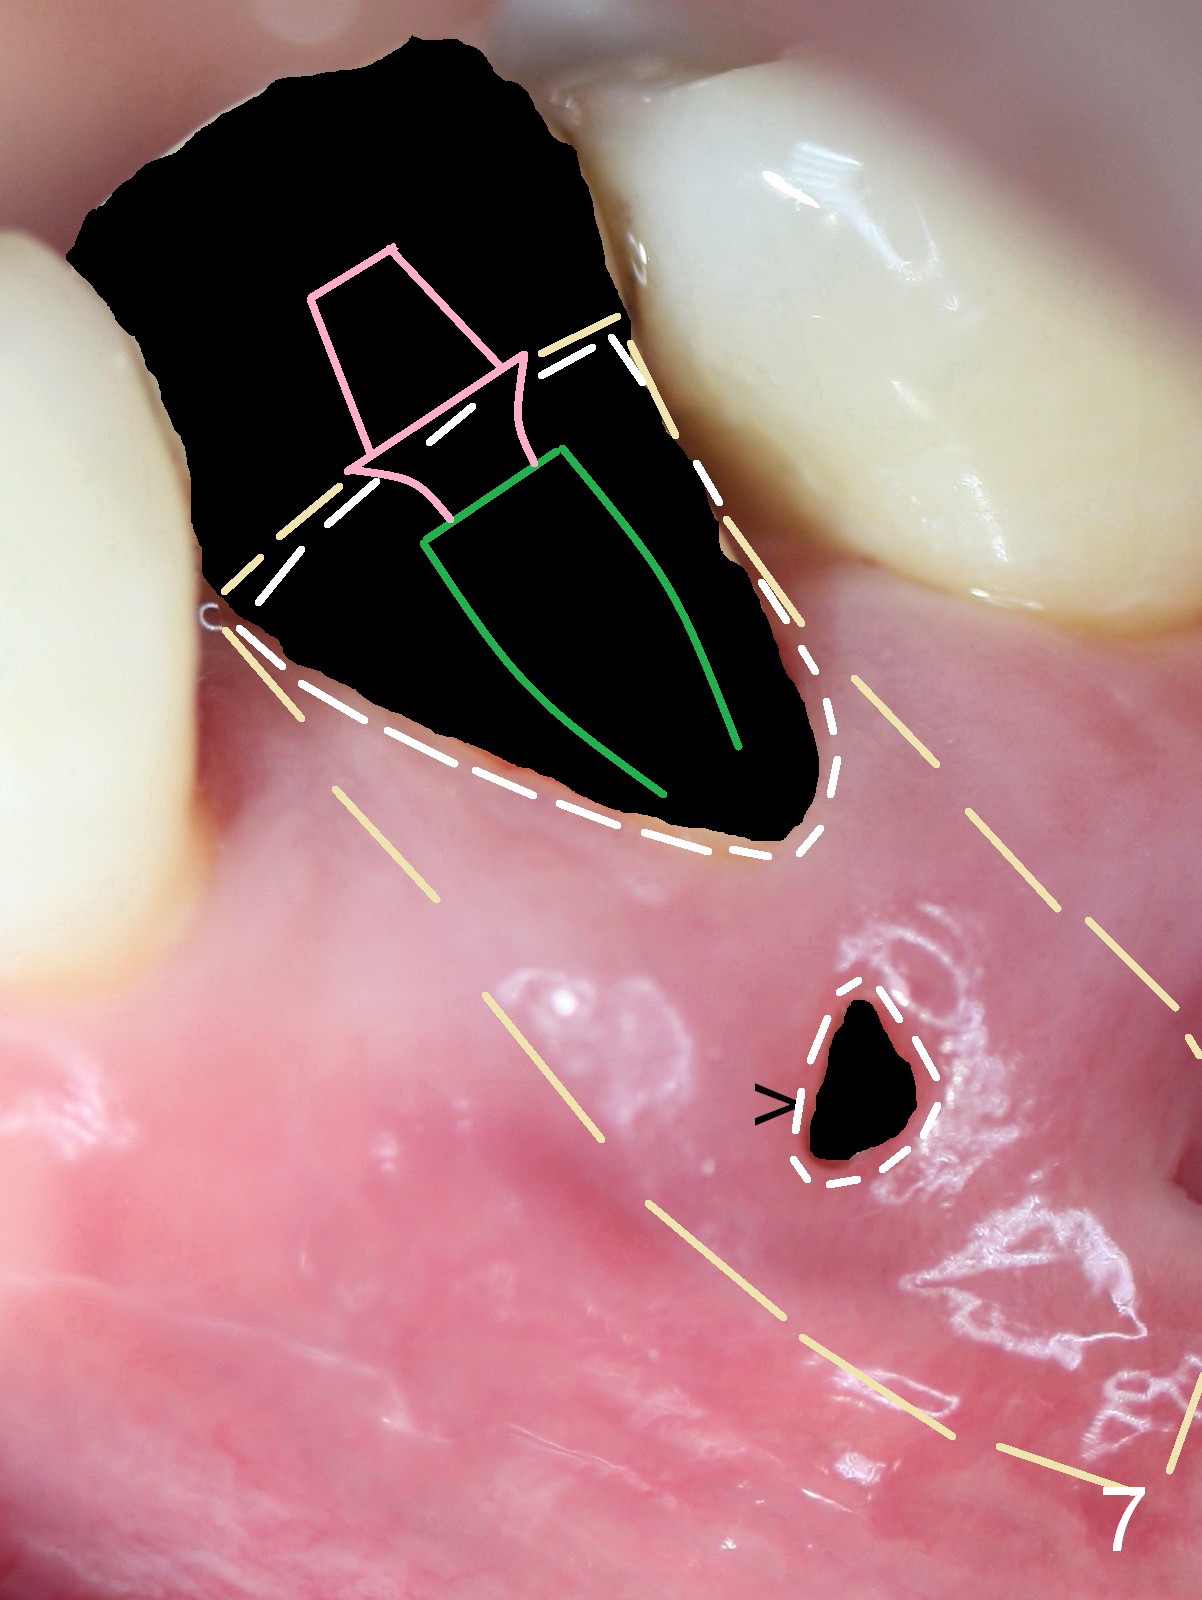

A 45-year-old man (JT) has endo failure at #20 with fenestration (Fig.1,2 black >) and fistula (white <). Insertion of a Gutta Percha at the fistula (Fig. 3 <; PA taken 2 years ago) indicates that the infection is dervied from the apex of the tooth #20. The socket will be soaked with 2% Xylo, 1:50,000 Epinephrine gauze. A 4.5x17 mm tissue-level (Fig.4) or 14 mm bone-level implant is placed as lingual as possible (Fig.5 green). If primary stability is achieved, an abutment is placed (pink). A large piece of resorbable membrane is used to cover the buccal defect (including buccal recession, fenestration and fistula (Fig.6 yellow dashed line). Two small pieces of non-resorbable membrane are placed to cover the gingival recession and the fenestration (Fig.7 white dashed line, buried underneath the edge of the gigniva). Then place bone graft buccally. Place a small piece of gauze (one layer) or plastic (from Tatum implant bag) over the 2nd membrane over the gingival recession and fabricate an immediate provisional. When the acrylic is partially set, remove the gauze or plastic from the provisional. After trimming and polishing, the provisional is cemented to securely keep the 2nd membrane in place. When the wound is healing and the 2nd membrane is stable, trim the buccal extension of the provisional. It is expected that the buccal hard and soft tissue will regenerate over the implant.